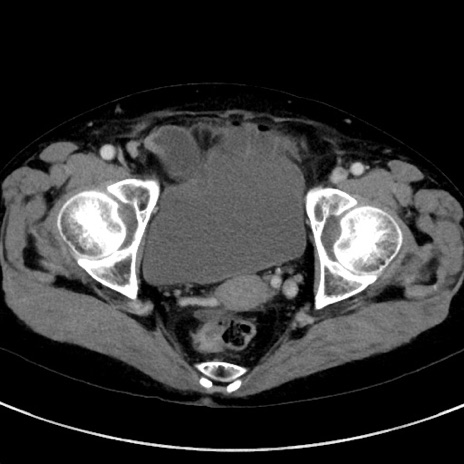

症例23(横断像)

【症例】70歳代女性

【主訴】下腹部痛・嘔吐

【現病歴】2日前より腹痛あり。昨日嘔吐あり。症状改善しないため来院。

【既往歴】胃GISTに対して胃部分切除後。

【身体所見】BT 37.1℃、BP 128/77mmHg、腹部:平坦・軟、下腹部に圧痛あり。

【データ】WBC 10200、CRP 0.31